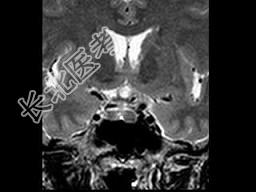

- 单项选择题女,25岁, 双侧泌乳,月经不调半年, 服药效果不佳,根据所提供图像, 最可能的诊断是 ( )

E、垂体微腺瘤